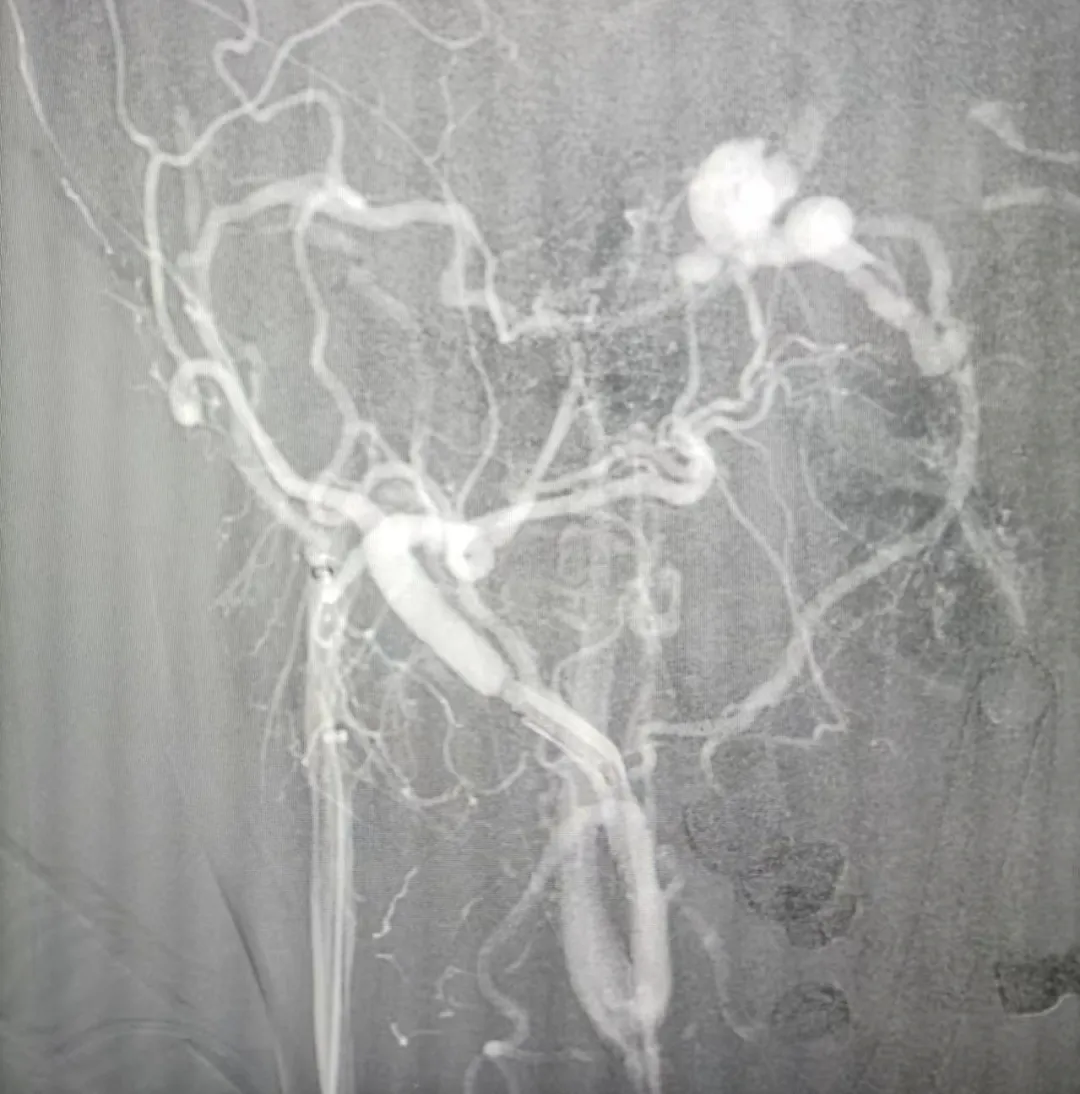

▲硬脑膜动静脉瘘口及扩张的眼上静脉

患者签字同意手术后,神外手术团队先予局麻下完成脑血管造影DSA,提示:右侧海绵窦区硬脑膜动静脉瘘(CS-dAVF),供血动脉为颈外动脉脑膜分支,引流静脉为眼上静脉,动静脉之间多个瘘口,动脉血直接灌入海绵窦,导致静脉高压,眼上静脉扩张迂曲,为球结膜充血、眼球外突的原因。脑血管造影DSA与入院颅脑颈部CTA结果不同,脑血管造影为诊断金标准。